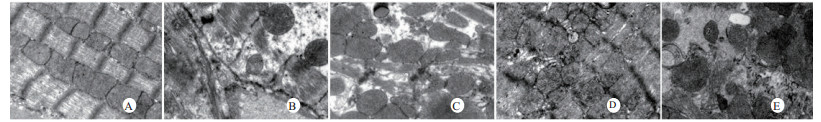

扫描电镜下可见,假手术组肺泡形态完整,肺泡壁光滑;感染性休克组肺泡明显压缩畸形,肺泡隔肿胀、扭曲、隆起;U50488H+感染性休克组肺泡形态大致完整,少数肺泡壁肿胀受损(图 5)。透射电镜下可见,假手术组心肌细胞形态正常;感染性休克组心肌细胞溶解、坏死、肌纤维断裂;U50488H+感染性休克组心肌细胞大致正常,无明显坏死(图 6)。假手术组肝细胞形态正常,毛细胆管未见扩张;感染性休克组肝细胞大片坏死,毛细胆管明显扩张;U50488H+感染性休克组肝细胞形态大致正常,毛细胆管略扩张(图 7)。假手术组肾小管上皮细胞形态狭长,核卵圆形,位于基底部;感染性休克组肾小管上皮断裂,微绒毛缺失;U50488H+感染性休克组肾小管上皮细胞大致正常,微绒毛不平滑,但无明显坏死(图 8)。

| A:假手术组,B:感染性休克组,C:U50488H+感染性休克组,D:nor-BNI+U50488H+感染性休克组,E:nor-BNI+感染性休克组 图 8 肾组织透射电镜检查(×15 000) Fig 8 Transmission electronic microscopic photos of kidney(×15 000) |